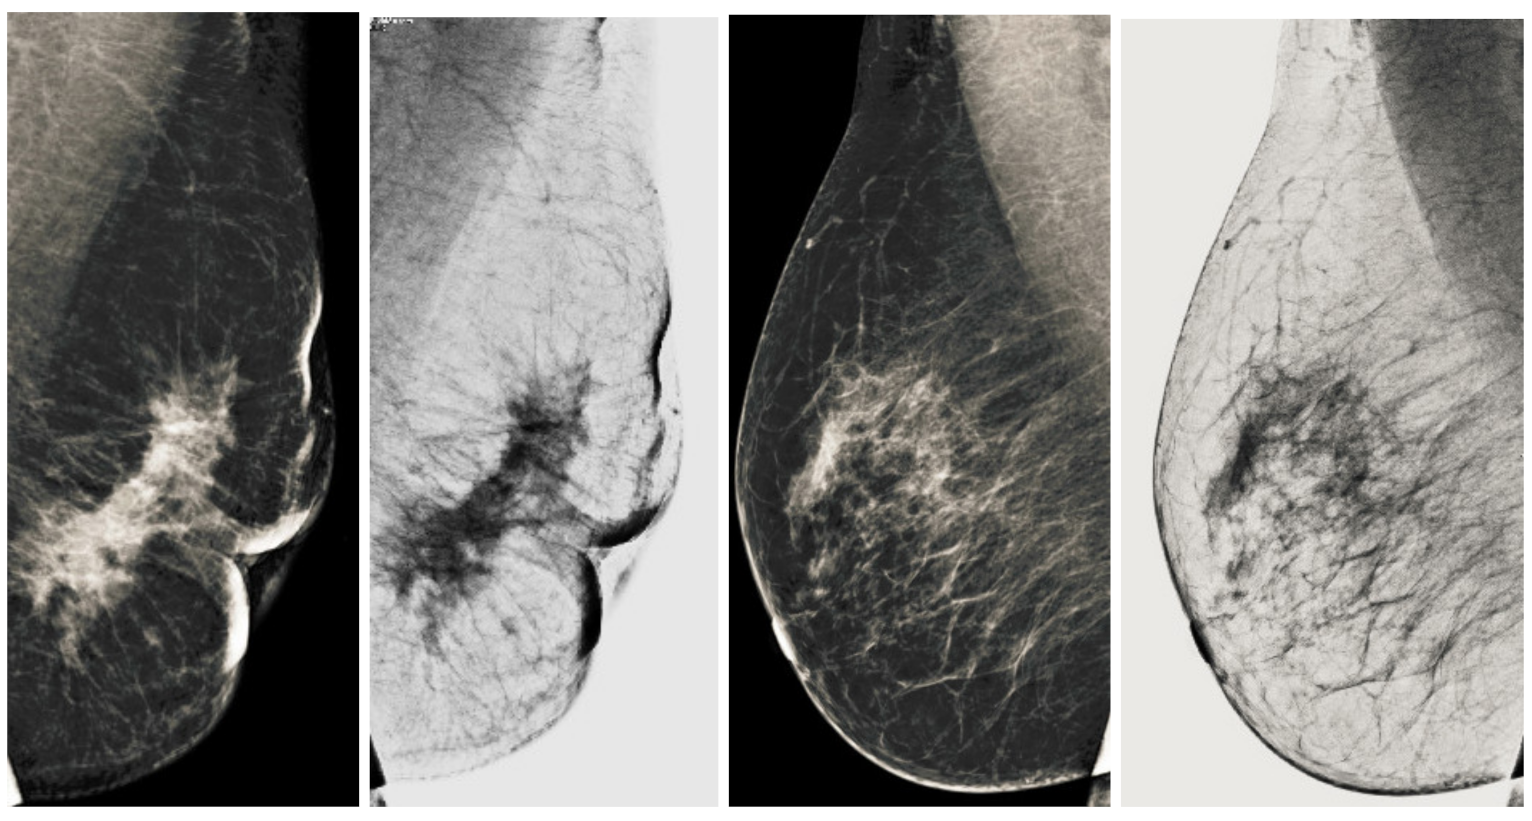

Computerized analysis of mammography is also challenging because one of the most important challenges is observing the pectoral muscles. The geometric shape of the pectoral muscles and their location depend on the mammographic images’ specific view [12,13]. There are two types of mammographic image views: the carnio-caudal (CC) view and the mediolateral oblique (MLO) view, and these views are shown in the Figure 1. The pectoral muscle on the CC view is semi-elliptical along the breast wall. In contrast, the MLO view covers most of the upper mammogram coverage and roughly corresponds to the overlapping right-angled triangle, as shown in Figure 1. Due to their appearance, both views suffered from low contrast, which made it difficult to see cancerous areas in some cases. Image enhancement requires correct observation and helps segment abnormal regions for disease classification. The quality of mammography images in terms of noise reduction and contrast enhancement is improved by using the image enhancement technique. The main purpose of implementing the image enhancement technique is to help the computerized breast cancer detection system to detect mammographic lesions with poor visibility and improve low contrast. Low contrast regions with small abnormalities are mostly hidden in the tissue of mammogram images, which makes it challenging to analyze the abnormal region, and also provides false detection.

Figure 1.

Representation of standard mammography views. The figure (a) represents the CC view of the right and left breast, and the figure (b) represents the MLO view of the right and left breast.